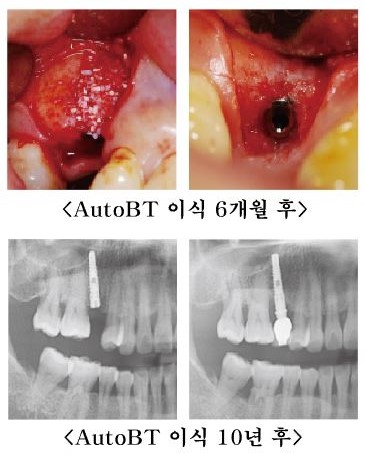

한국치아은행이 공개한 파우더형 자가치아골이식재 AutoBT의 Long term case 은 발치한 지 3년 이상 방치되어 골흡수가 많이 진행되고, bone의 healing이 잘 이루어지지 않은 상태에서 수술이 이루어진 것이 특징이다.

임플란트 식립 후 노출된 협측 총 길이만큼의 자가치아골이식재 AutoBT를 이식하고 6개월 뒤인 2차 수술시 생성된 뼈의 모습에서 보면 10개월 뒤 인공치아 장착, 4년, 5년, 8년, 10년 의 자세한 F/U 기록과 함께 X-ray와 임상사진을 통해 건강한 gingiva texture와 buccal bone volume, 깨끗한 Implant neck area를 확인할 수 있다.